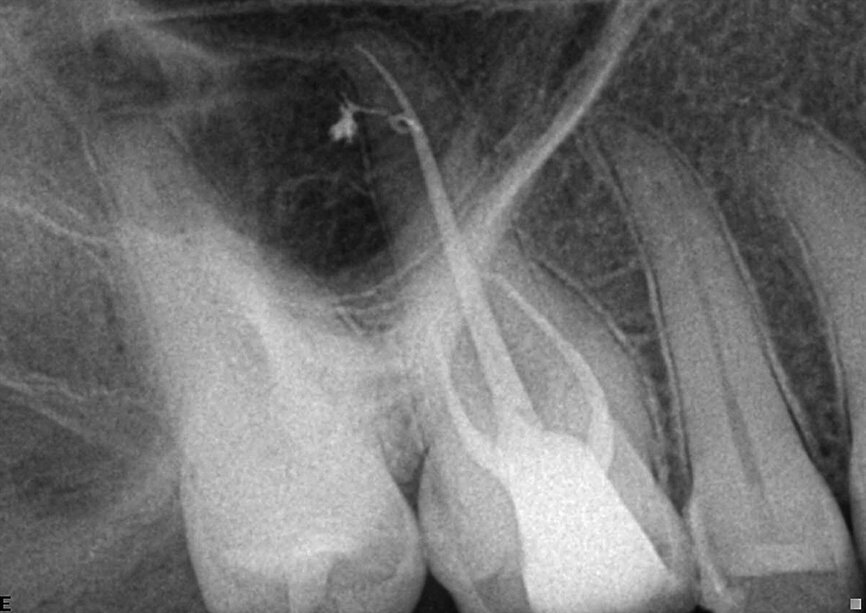

Fig. 7: A failing root canal treatment with apical infection and an internal resorption in the apical area.

Fig. 8: The follow-up confirms a fast healing of both the apical area and the area of the resorption lesion.

The case of a failing root canal treatment with apical infection and an internal resorption in the apical area was referred to us (Fig. 7). After removing the previous filling, chemical preparation was performed, with the help of the partial vacuum inside the system the chemicals were able to clean the resorption area without an aggressive effect on the periodontal ligament; this has led to a truly three-dimensional obturation. The 4-month follow-up image (Fig. 8) confirms a fast healing of both the apical area and the area of the resorption lesion.